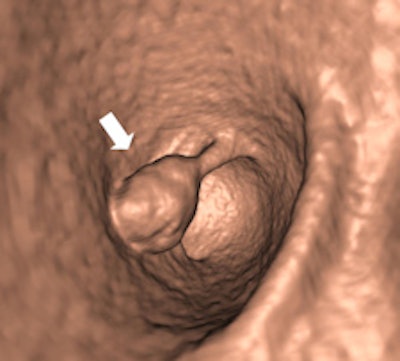

Left: Large pedunculated polyp in the sigmoid (white arrow). Right: Corresponding 3D image of this pedunculated polyp with a 2-cm head (white arrow). Images courtesy of Philippe Lefere, MD.Moreover, the procedure is patient-friendly and it can be performed on an outpatient basis. No sedation is necessary, the examination time is short, it can be performed the same day as the optical colonoscopy, it can detect important pathology outside of the colon, and patient preparation is possible without interruption of normal daily activities, Lefere said. The main drawbacks are that radiation is used, polypectomy is not possible, there is the potential for superfluous explorations (iatrogenic pathology), patient preparation is still needed, it involves a relatively steep learning curve, and long interpretation times during the initial phase.